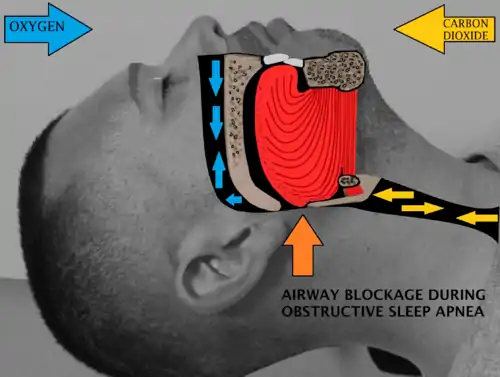

Sleep surgery is a surgery performed to treat sleep disordered breathing. Sleep disordered breathing is a spectrum of disorders that includes snoring, upper airway resistance syndrome, and obstructive sleep apnea. These surgeries are performed by surgeons trained in otolaryngology, oral maxillofacial surgery, and craniofacial surgery.

Obstructive sleep apnea or sleep apnea is defined as either cessation of breathing (apnea) for 10 seconds, or a decrease in normal breathing (hypopnea) with an associated desaturation in oxygen and arousal during sleep that lasts at least 10 seconds. In adults, it is typical to have up to 4.9 events per hour. In obstructive sleep apnea, affected individuals are categorized based on how many apneas or hypopneas (apnea-hypopnea index or AHI) or events they have per hour.